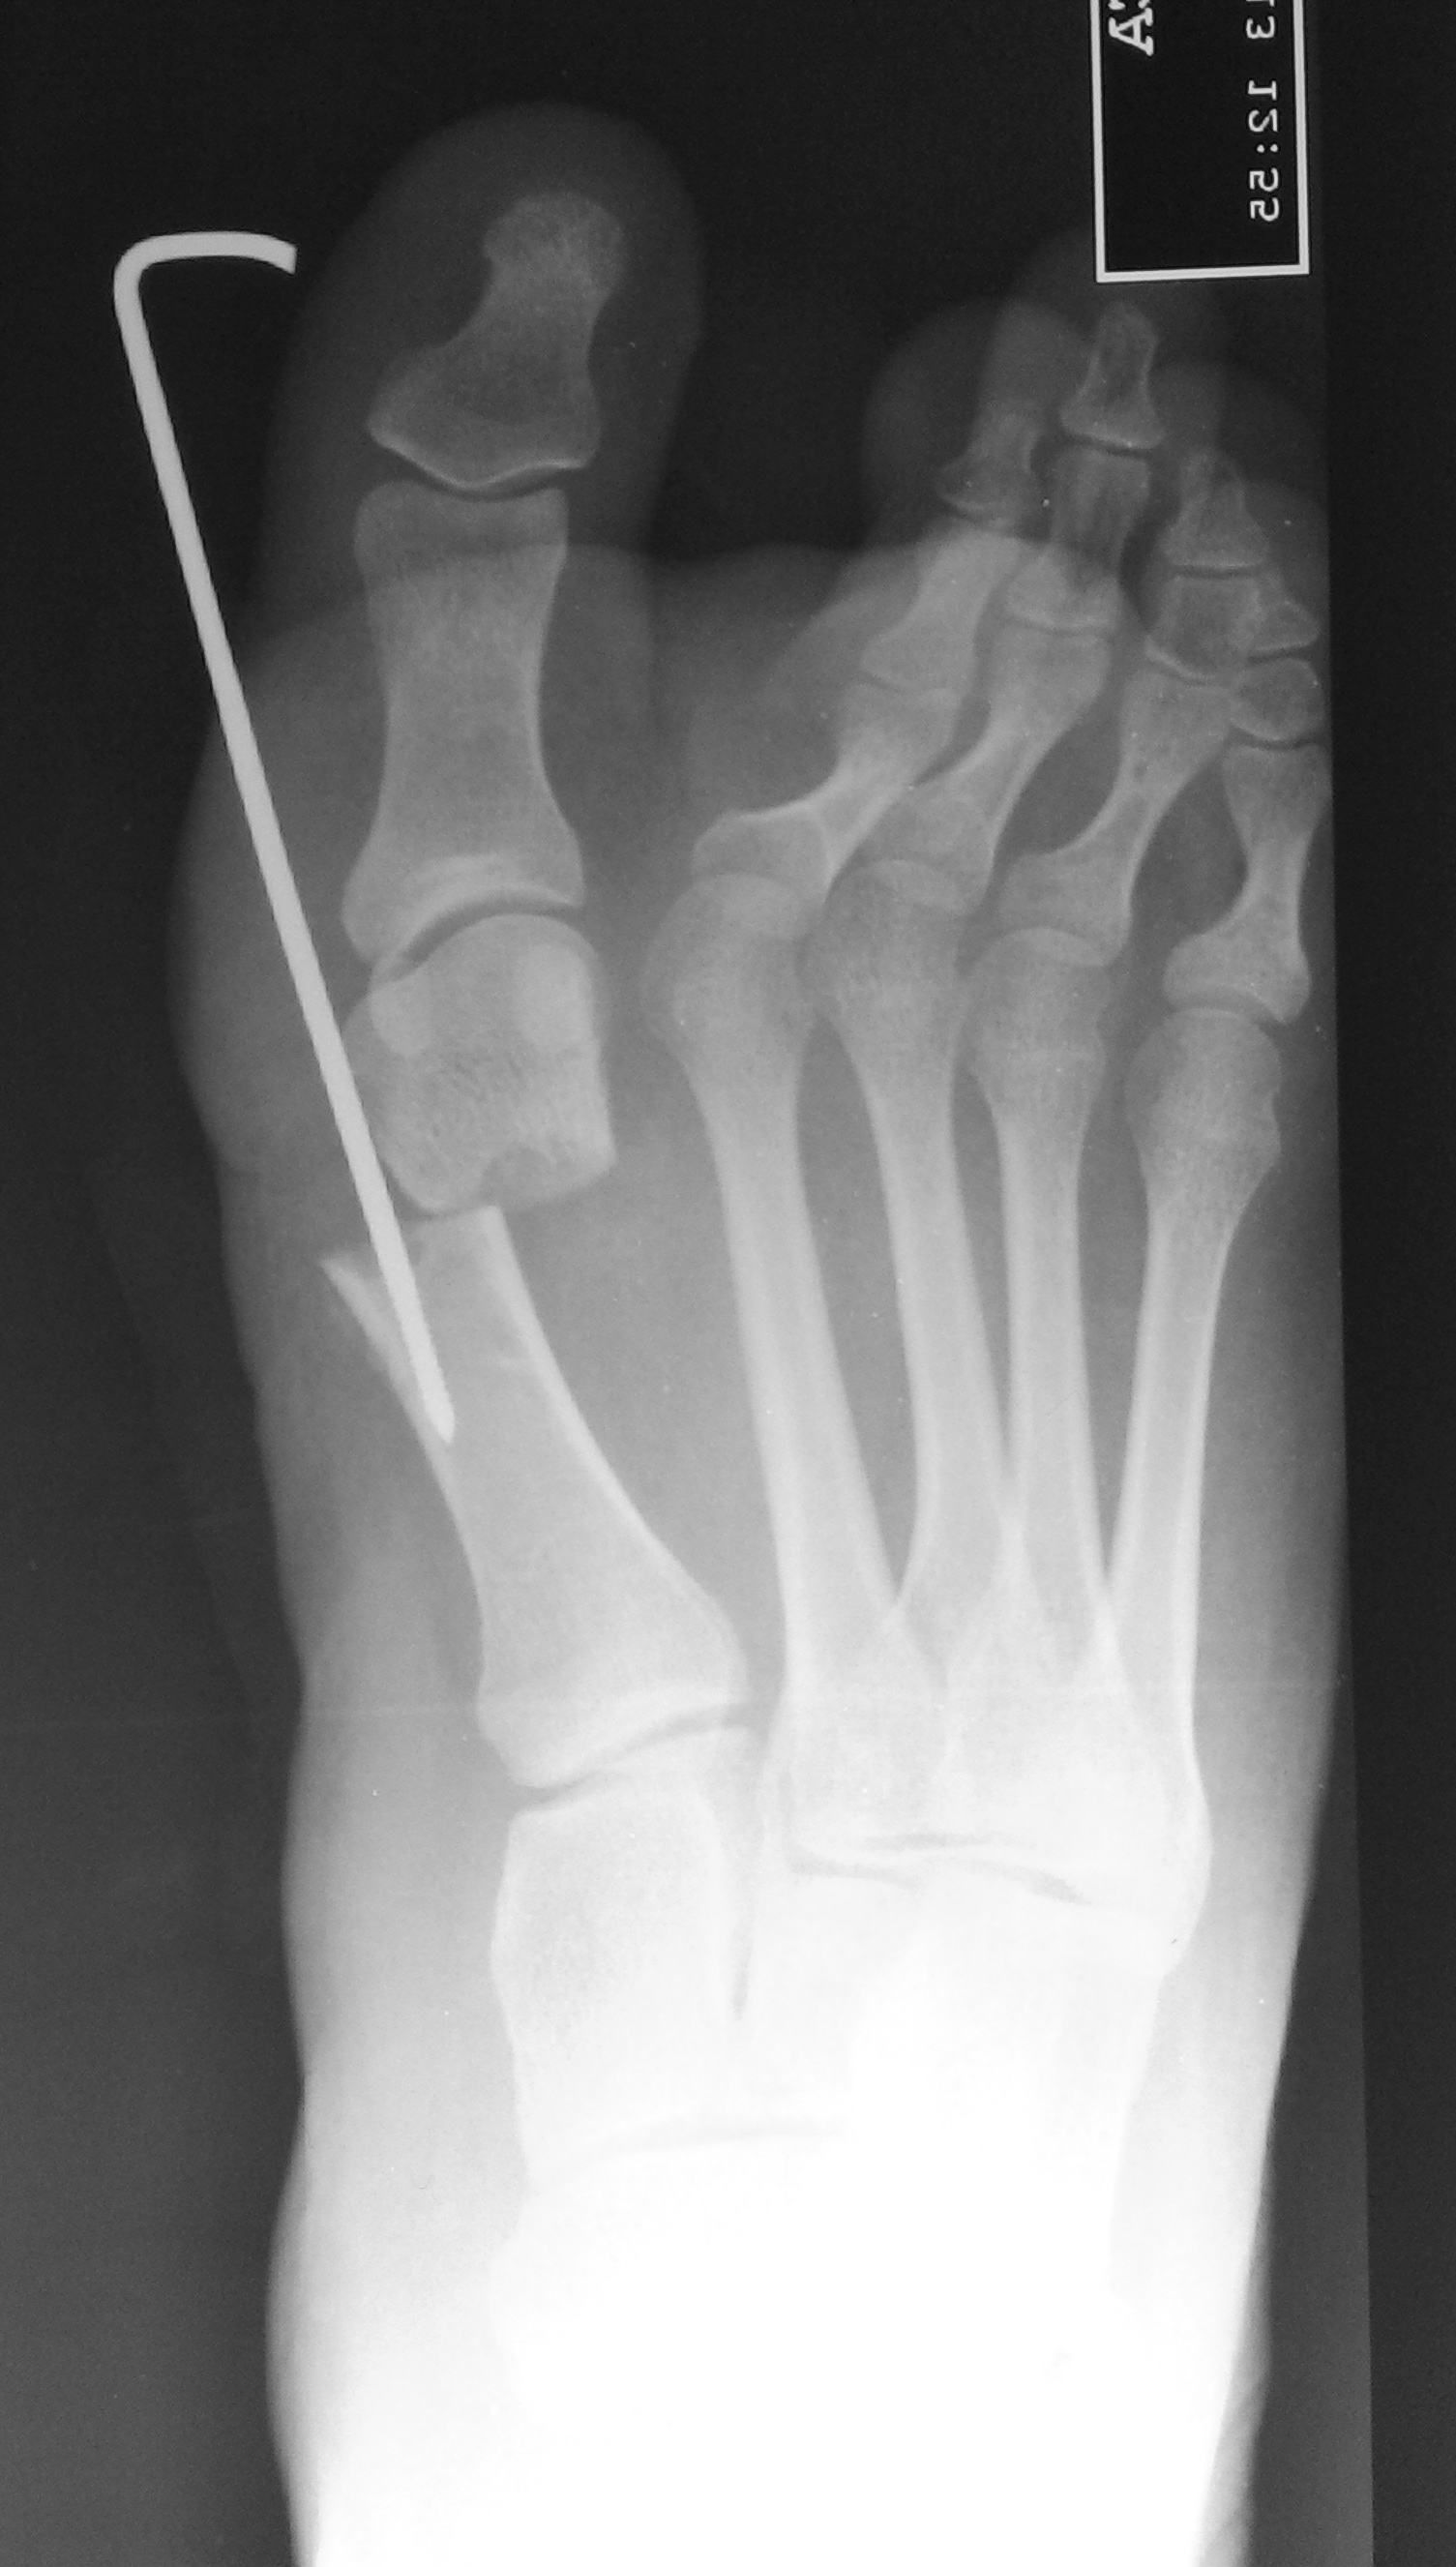

Osteotomía percutánea de Bosch ¿El paciente acepta la clavija? Análisis clínico – funcional y resultados a corto plazo. [Bosch percutaneous osteotomy. Does the patient accept the nail? Clinical and functional analysis and short-term result.]

8 Bösch P, Markowski H, Rannicher V. Technik und erste ergebnisse der subkutanen distalen metatarsale-I-osteotomie. Orthopädische Praxis 1990;26:51-6.

17 Sotelano P, Migues A. Tratamiento percutáneo del hallux valgus. Técnica de Bosch. Rev Asoc Argent Ortop Traumatol 2007;72:233-41.

19 Bösch P, Wanke S, Legenstein R. Hallux valgus correction by the method of Bösch: a new technique with a seven-to-ten-year follow-up. Foot Ankle Clin 2000;5:485-98.